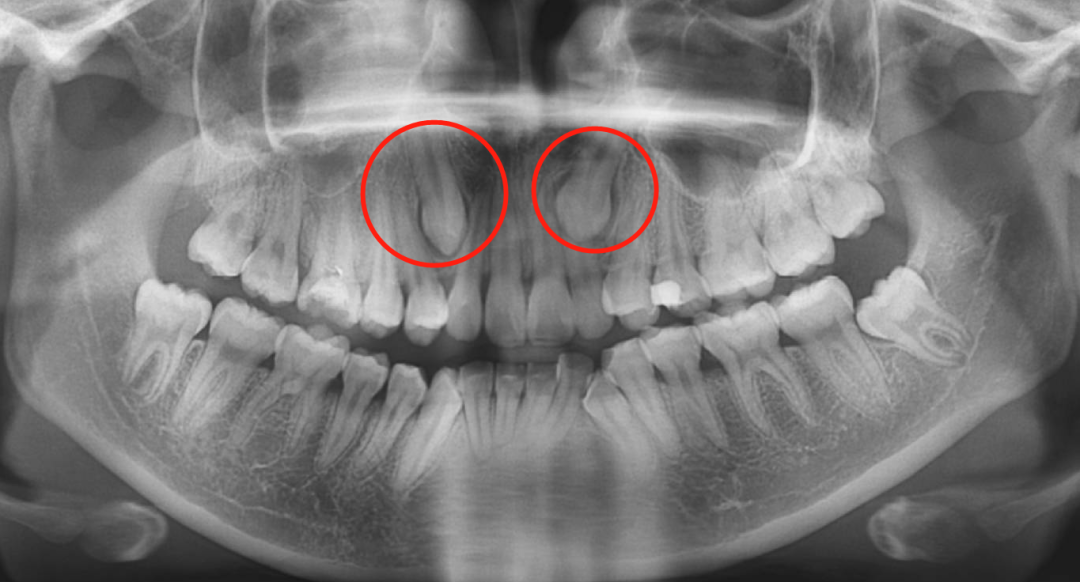

🔎埋伏牙

X光拍片为什么要等看牙为什么要拍片?非专业人士如何看懂自己的牙片!_https://www.jmylbn.com_新闻资讯_第13张